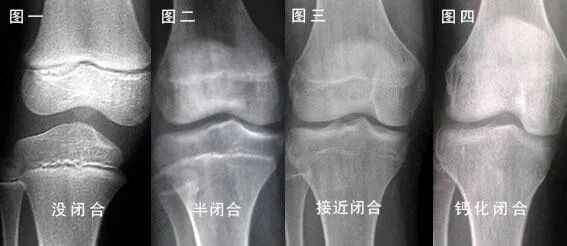

「骨骺线」是指长骨干骺端与骨骺之间的一盘软骨结构,又称为「骺板」或「生长板」。

在幼儿的X光片上呈现为一条较宽的透光带。

人体每根长骨的两头都有骨骺线,是用于生长的软骨,它会随着我们的营养吸收,与内分泌激素的作用下不断的骨化。

骨化完全后,就形成了一条紧密的缝,此时骨骺线完全闭合,骨骼也会停止生长!